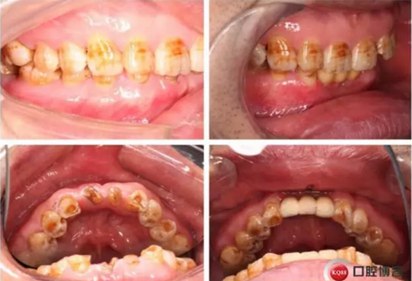

下圖是術后照片 治療過程 術前測量上下牙長度比例,確定水激光冠延長深度約3mm,拔除31、41,在術區(qū)減低牙槽嵴高度,32、42位點種植MINI型一段式種植體,使用臨時愈合帽行暫時性修復。

治療前后照片顯示患者上下臨床牙冠比例協(xié)調(diào),患者對臨時修復體效果十分滿意。當然有待后期愈合及長期的臨床隨訪,以觀察遠期臨床效果。將水激光應用臨床冠延長,有利于精準去除骨量,利于術后愈合。而MINI型一段式種植體滿足骨寬度不足,及臨時修復打下堅實基礎。